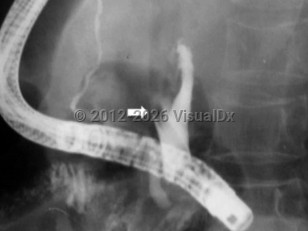

AscariasisAscariasis

Fasciolopsiasis

Taeniasis

Tuberculous enteritis